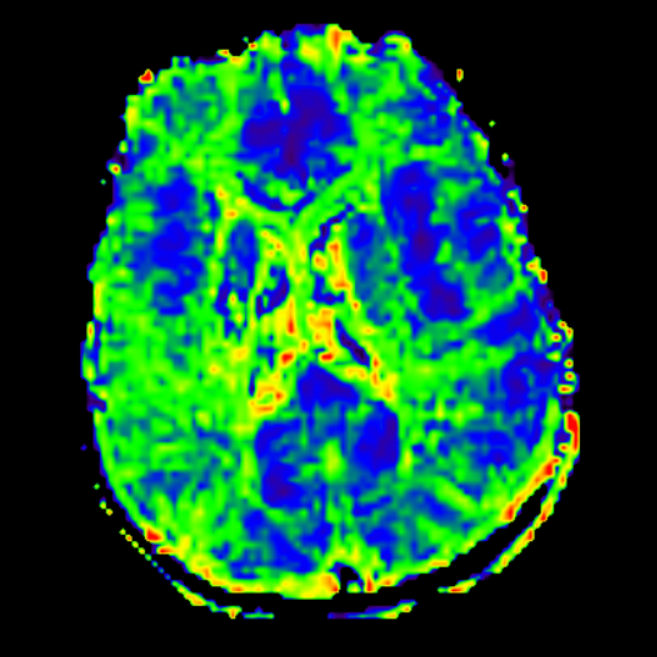

术前影像学资料(MRI)

磁共振灌注

TTP

MTT

影像学的随访

术后18月MR

术后18月MR

术后18月MR,缺血较前改善。

TTP

MTT

2.可行性:术前完善高分辨磁共振、DSA以及血流动力学,结合患者病情制定合理手术策略;